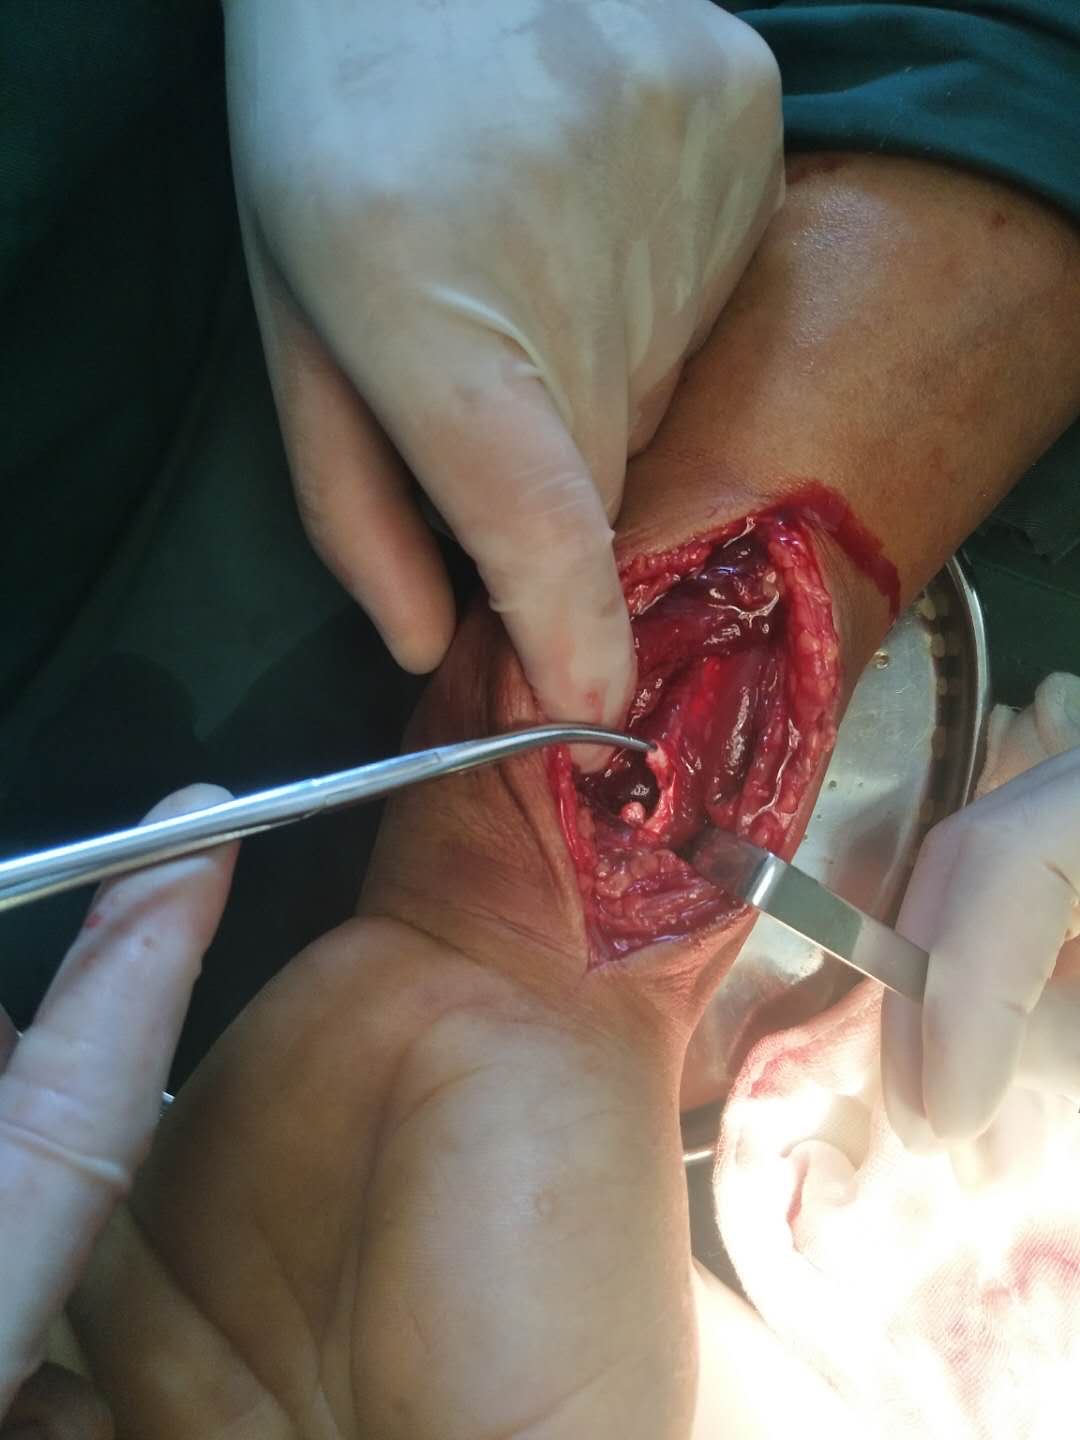

生命体征平稳,心肺复未见异常。左腕部肿胀明显,畸形,皮色发红,皮温高,压痛及纵向叩击痛阳性,拇指屈指受限,正中神经支配区各指麻木,末梢血运正常。

在臂丛麻醉下行切复内固定术,肌腱吻合术,术后制动,营养神经等处理。